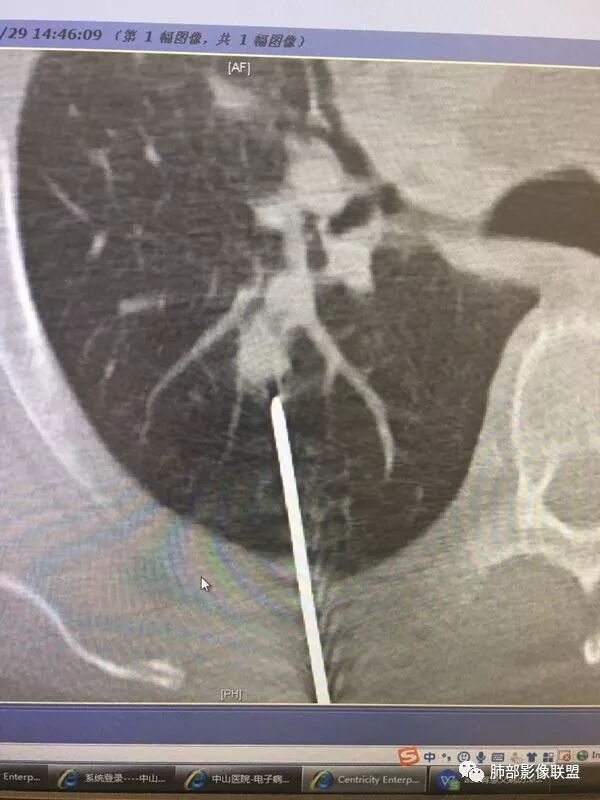

病灶从2月份就开始有,应该最早说是1月7号就有了,到3月13号稍微增大一点,到后面几乎没变化,到5月份好像稍微大一些,炎性应该是炎性,犹豫的是这个炎性到底什么病变呢?其实本没变化,它特点一个是在叶裂上,跟血管关系密切,但是病灶边缘稍收缩,病灶没有太大变化。

因为这个长轴似乎跟支气管走行一致的,其实治疗效果不是很理想,我先把性质定为炎性。因为这个病灶它沿着血管支气管走行的方向,大家都考虑隐球菌,这么久病灶无明显变化,它跟血管束关系很密切。我犹豫就在此,到底是IgG4还是隐球,大方向是炎性,不符合的就是也在激素治疗。